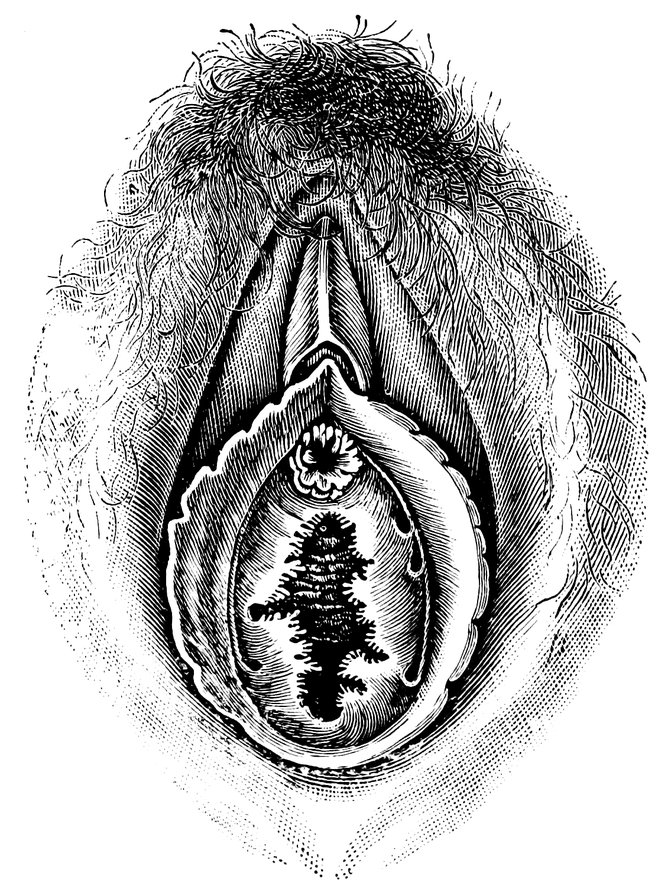

| 44. | Carunculæ Myrtiformes in a Primipara | 71 |

| 45. | Vaginal Inlet of a Multipara, without Carunculæ Myrtiformes. Slight Prolapse of Anterior and Posterior Vaginal Walls | 71 |

| 48. | The female pudendum, or vulva, with the labia majora | 204 |

| 49. | Vestibule of the vagina, with the labia minora or nymphæ, etc | 205 |